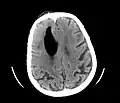

CT scans of patients with a tension pneumocephalus typically show air that compresses the frontal lobes of the brain, which results in a tented appearance of the brain in the skull known as the Mount Fuji sign.[1][2][3] The name is derived from the resemblance of the brain to Mount Fuji in Japan, a volcano known for its symmetrical cone. In typical cases, there is a symmetrical depression near the midline (such as the crater of a volcano), due to intact bridging veins.[3] Its occurrence seems to be limited to tension pneumocephalus (not occurring in pneumocephalus without tension).[4] The sign was first described by a team of Japanese neurosurgeons.[5]

Additional images

Large pneumocephaly secondary to surgical wound